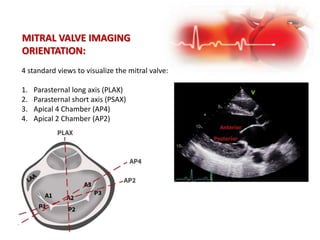

MITRAL VALVE IMAGING

ORIENTATION:

4 standard views to visualize the mitral valve:

1. Parasternal long axis (PLAX)

2. Parasternal short axis (PSAX)

3. Apical 4 Chamber (AP4)

4. Apical 2 Chamber (AP2)

APICAL 4 CHAMBER (AP4)